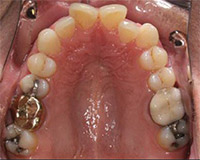

Check out this 48-year-old man’s case where preserving the existing occlusion is a breeze. No bond failures, no wires and appointments that take 10 minutes or less. The patient’s overbite though, proved to have multiple solutions. Which would you choose?